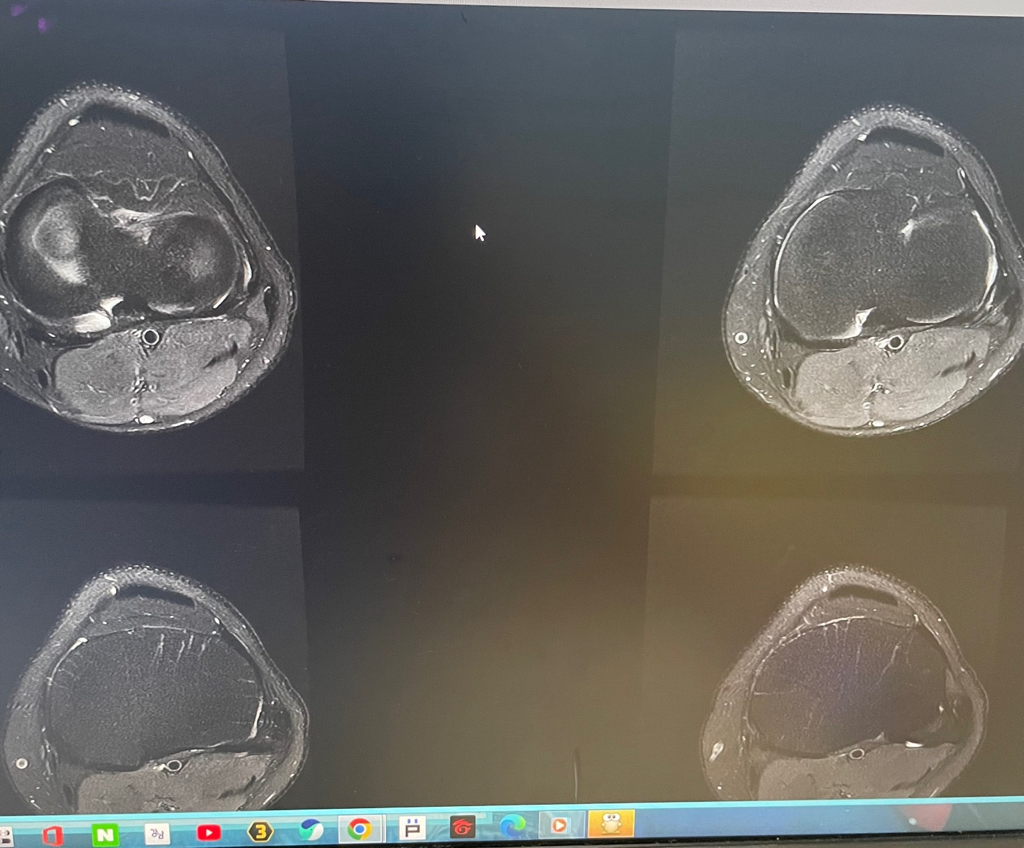

무릎 mri 원형원골인지 봐주실 수 있을까요

무릎이 너무 자주 아파서 mri를 찍어봤는데 무릎 연골에 이상이 있을까요

무릎이 선천적으로 원형연골인지 봐주시면 감사하겠습니다

MRI 판독에는 퇴행성 연골 손상, 바깥쪽 원판형 반월상 연골 이 의심된다고 적혀 있습니다.